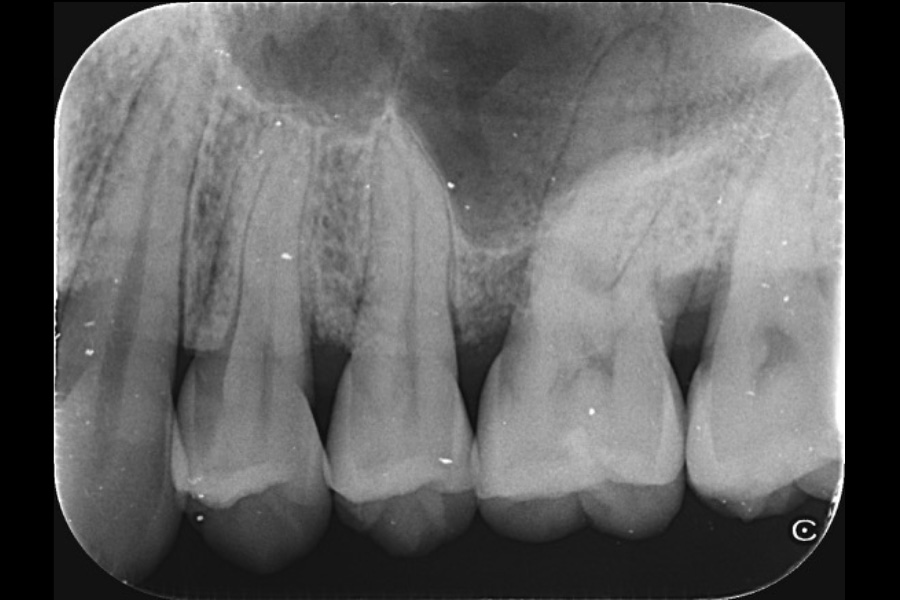

左上奥歯の歯ぐきがむずむずして出血する

【歯周組織再生療法】

- 主訴

- 左上奥歯の歯ぐきがむずむずして出血する

- 治療内容

- 左上3遠心に垂直性骨吸収が認められたためエムドゲインと骨補填材を用いて歯周組織再生療法を行った

- 治療に伴うリスク

- 歯肉退縮、知覚過敏